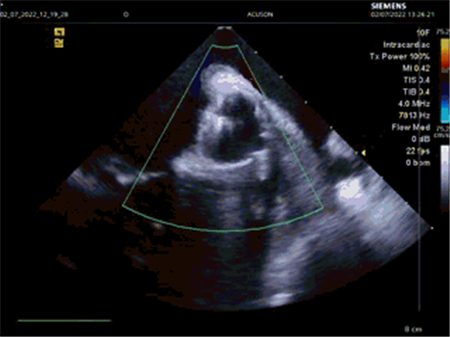

手术在局麻下实施,患者在完全清醒的状态下完成了手术。心内科分别使用了两套不同的介入治疗辅助系统完成手术。首先在脉冲消融系统下进行了房颤消融,然后再使用心腔内超声+Carto三维标测系统进行左心耳封堵。据了解,房颤脉冲消融+左心耳封堵这样的一站式手术,在国内目前没有看到相关报道。

超声下显示左心耳完全封堵